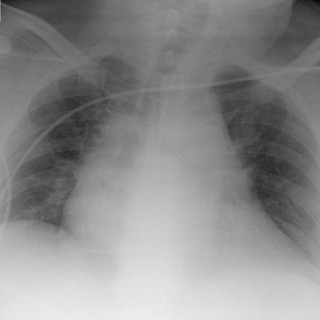

Ved Barneklinikken ved Oslo universitetssykehus, Ullevål, ble det lagt inn en 15 måneder gammel jente med feberperioder, blekhet, forstørret lever og milt. Blodprøver viste anemi, leukopeni, trombocytopeni, høyt ferritinnivå og høyt CRP-nivå. Pasienten viste seg å ha den sjeldne tilstanden hemofagocytisk lymfohistiocytose (HLH), som var utløst av en i Norge meget sjelden infeksjonssykdom, nemlig visceral leishmaniasis. Forfatterne presenterer en problemorientert utrednings- og behandlingsprosess. For en barnelege er dette meget interessant å følge, trolig også for leger innen andre deler av...